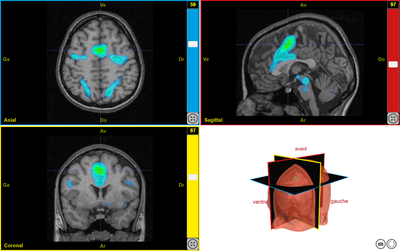

plaisir1

Image dans sa taille originale :

Ancien logiciel : EduAnatomist et Neuropeda

Informations sur les images AnaPeda

Exemple de lien direct vers EduAnat 2 en ligne